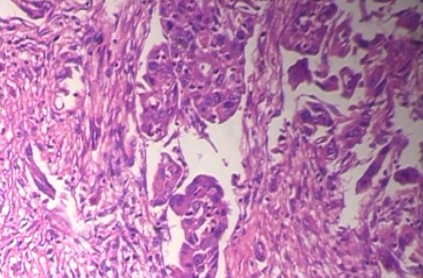

Background: Breast cancer has the highest prevalence in women globally. The classification and diagnosis of breast cancer and its histopathological images have always been a hot spot of clinical concern. In Computer-Aided Diagnosis (CAD), traditional classification models mostly use a single network to extract features, which has significant limitations. On the other hand, many networks are trained and optimized on patient-level datasets, ignoring the application of lower-level data labels. Method: This paper proposes a deep ensemble model based on image-level labels for the binary classification of benign and malignant lesions of breast histopathological images. First, the BreakHis dataset is randomly divided into a training, validation and test set. Then, data augmentation techniques are used to balance the number of benign and malignant samples. Thirdly, considering the performance of transfer learning and the complementarity between each network, VGG-16, Xception, Resnet-50, DenseNet-201 are selected as the base classifiers. Result: In the ensemble network model with accuracy as the weight, the image-level binary classification achieves an accuracy of $98.90\%$. In order to verify the capabilities of our method, the latest Transformer and Multilayer Perception (MLP) models have been experimentally compared on the same dataset. Our model wins with a $5\%-20\%$ advantage, emphasizing the ensemble model's far-reaching significance in classification tasks. Conclusion: This research focuses on improving the model's classification performance with an ensemble algorithm. Transfer learning plays an essential role in small datasets, improving training speed and accuracy. Our model has outperformed many existing approaches in accuracy, providing a method for the field of auxiliary medical diagnosis.